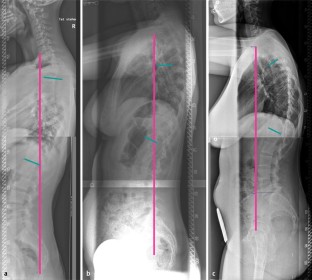

Abb. 1